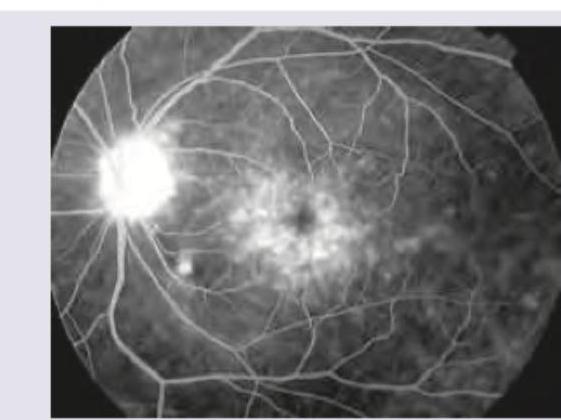

The FFA given below shows:

Explanation: ***Flower petal appearance*** - This appearance is characteristic of **macular edema** on fluorescein angiography, specifically **cystoid macular edema**. - The dye leaks from perifoveal capillaries and accumulates in the intraretinal cystic spaces, outlining the **Henle's layer** in a radial, flower-petal-like pattern. *Ink blot pattern* - The **ink blot pattern** is seen in **central serous chorioretinopathy** where fluorescein leaks from a single point in the retinal pigment epithelium into the subretinal space, gradually expanding. - This differs from the multifocal cystic accumulation seen in the image. *Smoke stack pattern* - The **smoke stack pattern** is another feature of **central serous chorioretinopathy**, characterized by vertical leakage of fluorescein that expands upwards like smoke from a chimney. - This is not consistent with the diffuse, radial pattern observed in the image. *Puff of smoke appearance* - The **puff of smoke appearance** is typically associated with **moyamoya disease**, an angiographic finding of abnormal collateral vessels at the base of the brain. - This term is unrelated to retinal fluorescein angiography findings.